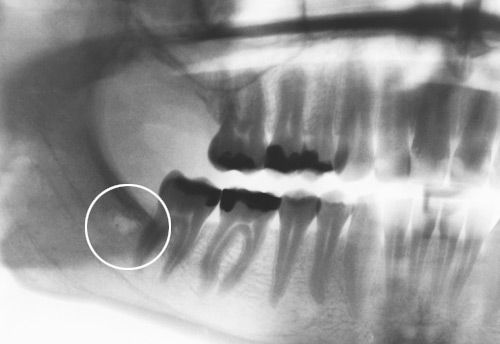

Bei der DentalReflex-Überprüfung wurde eine deutliche Belastung im Bereich des 18./19. festgestellt. Es war vor Jahren eine Extraktion des 18. vorgenommen wurden. Da der Kieferknochen in diesem Bereich laut DentalReflex-Testung einen Herd aufwies, wurde eine OP in diesem Bereich vorgenommen. Nach dieser OP waren die oben angegebenen Beschwerden ohne andere Therapien für einen Zeitraum von 8 Wochen völlig verschwunden! Nach ca. 12 Wochen waren die gleichen Beschwerden wieder vorhanden. Bei einer erneuten Testung wurde festgestellt, dass im Kieferknochen Regio 48 eine Belastung vorhanden war. Der Patient gab an, dass in diesem Bereich nie ein Weisheitszahn gezogen wurde und dass dieser Zahn auch nicht angelegt war.

Auch bei gründlicher Inspektion des Leerkieferabschnittes im Bereich des 4. Quadranten konnte optisch kein Herd oder Störfeld ausgemacht werden. Es wurde trotzdem ein OP-Termin vereinbart, weil der Patient angab, dass er immer, wenn er über die entsprechende Zahnzone des 48. behandelt wurde, tagelang keine nennenswerten Schmerzen und Bewegungseinschränkungen mehr hatte. Dieser Test der Störfeldbeeinflussung über die entsprechenden Reflexzonen ist viermal gemacht worden, mit immer den gleichen positiven Ergebnissen. Das war der Grund, warum der Patient sich schließlich zu einer Operation entschloss.